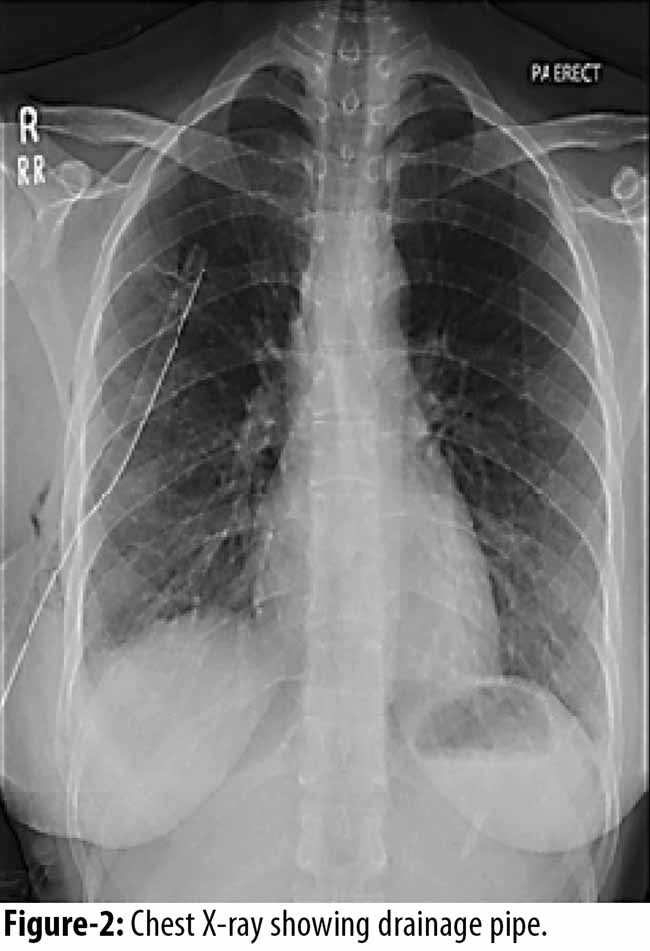

The patient was admitted and right sided tube thoracostomy was done and the chest tube was put on suction followed by chest physiotherapy. A repeat chest x-ray showed re-expansion of lung and gradual resolution of pneumothorax (Figure-2)

In our case, the patient presented with chest pain, shortness of breath and cough during menstruation, indicating all the classical symptoms of CP. The X-ray revealed a right sided pneumothorax. The patient first went through thoracostomy with some lung physiotherapy and then to stop the recurrence VATS was the procedure of choice, in order to investigate the etiology as well as offer treatment in the form of Pleurodesis. She was kept in observation and then was discharged healthy with no pain.